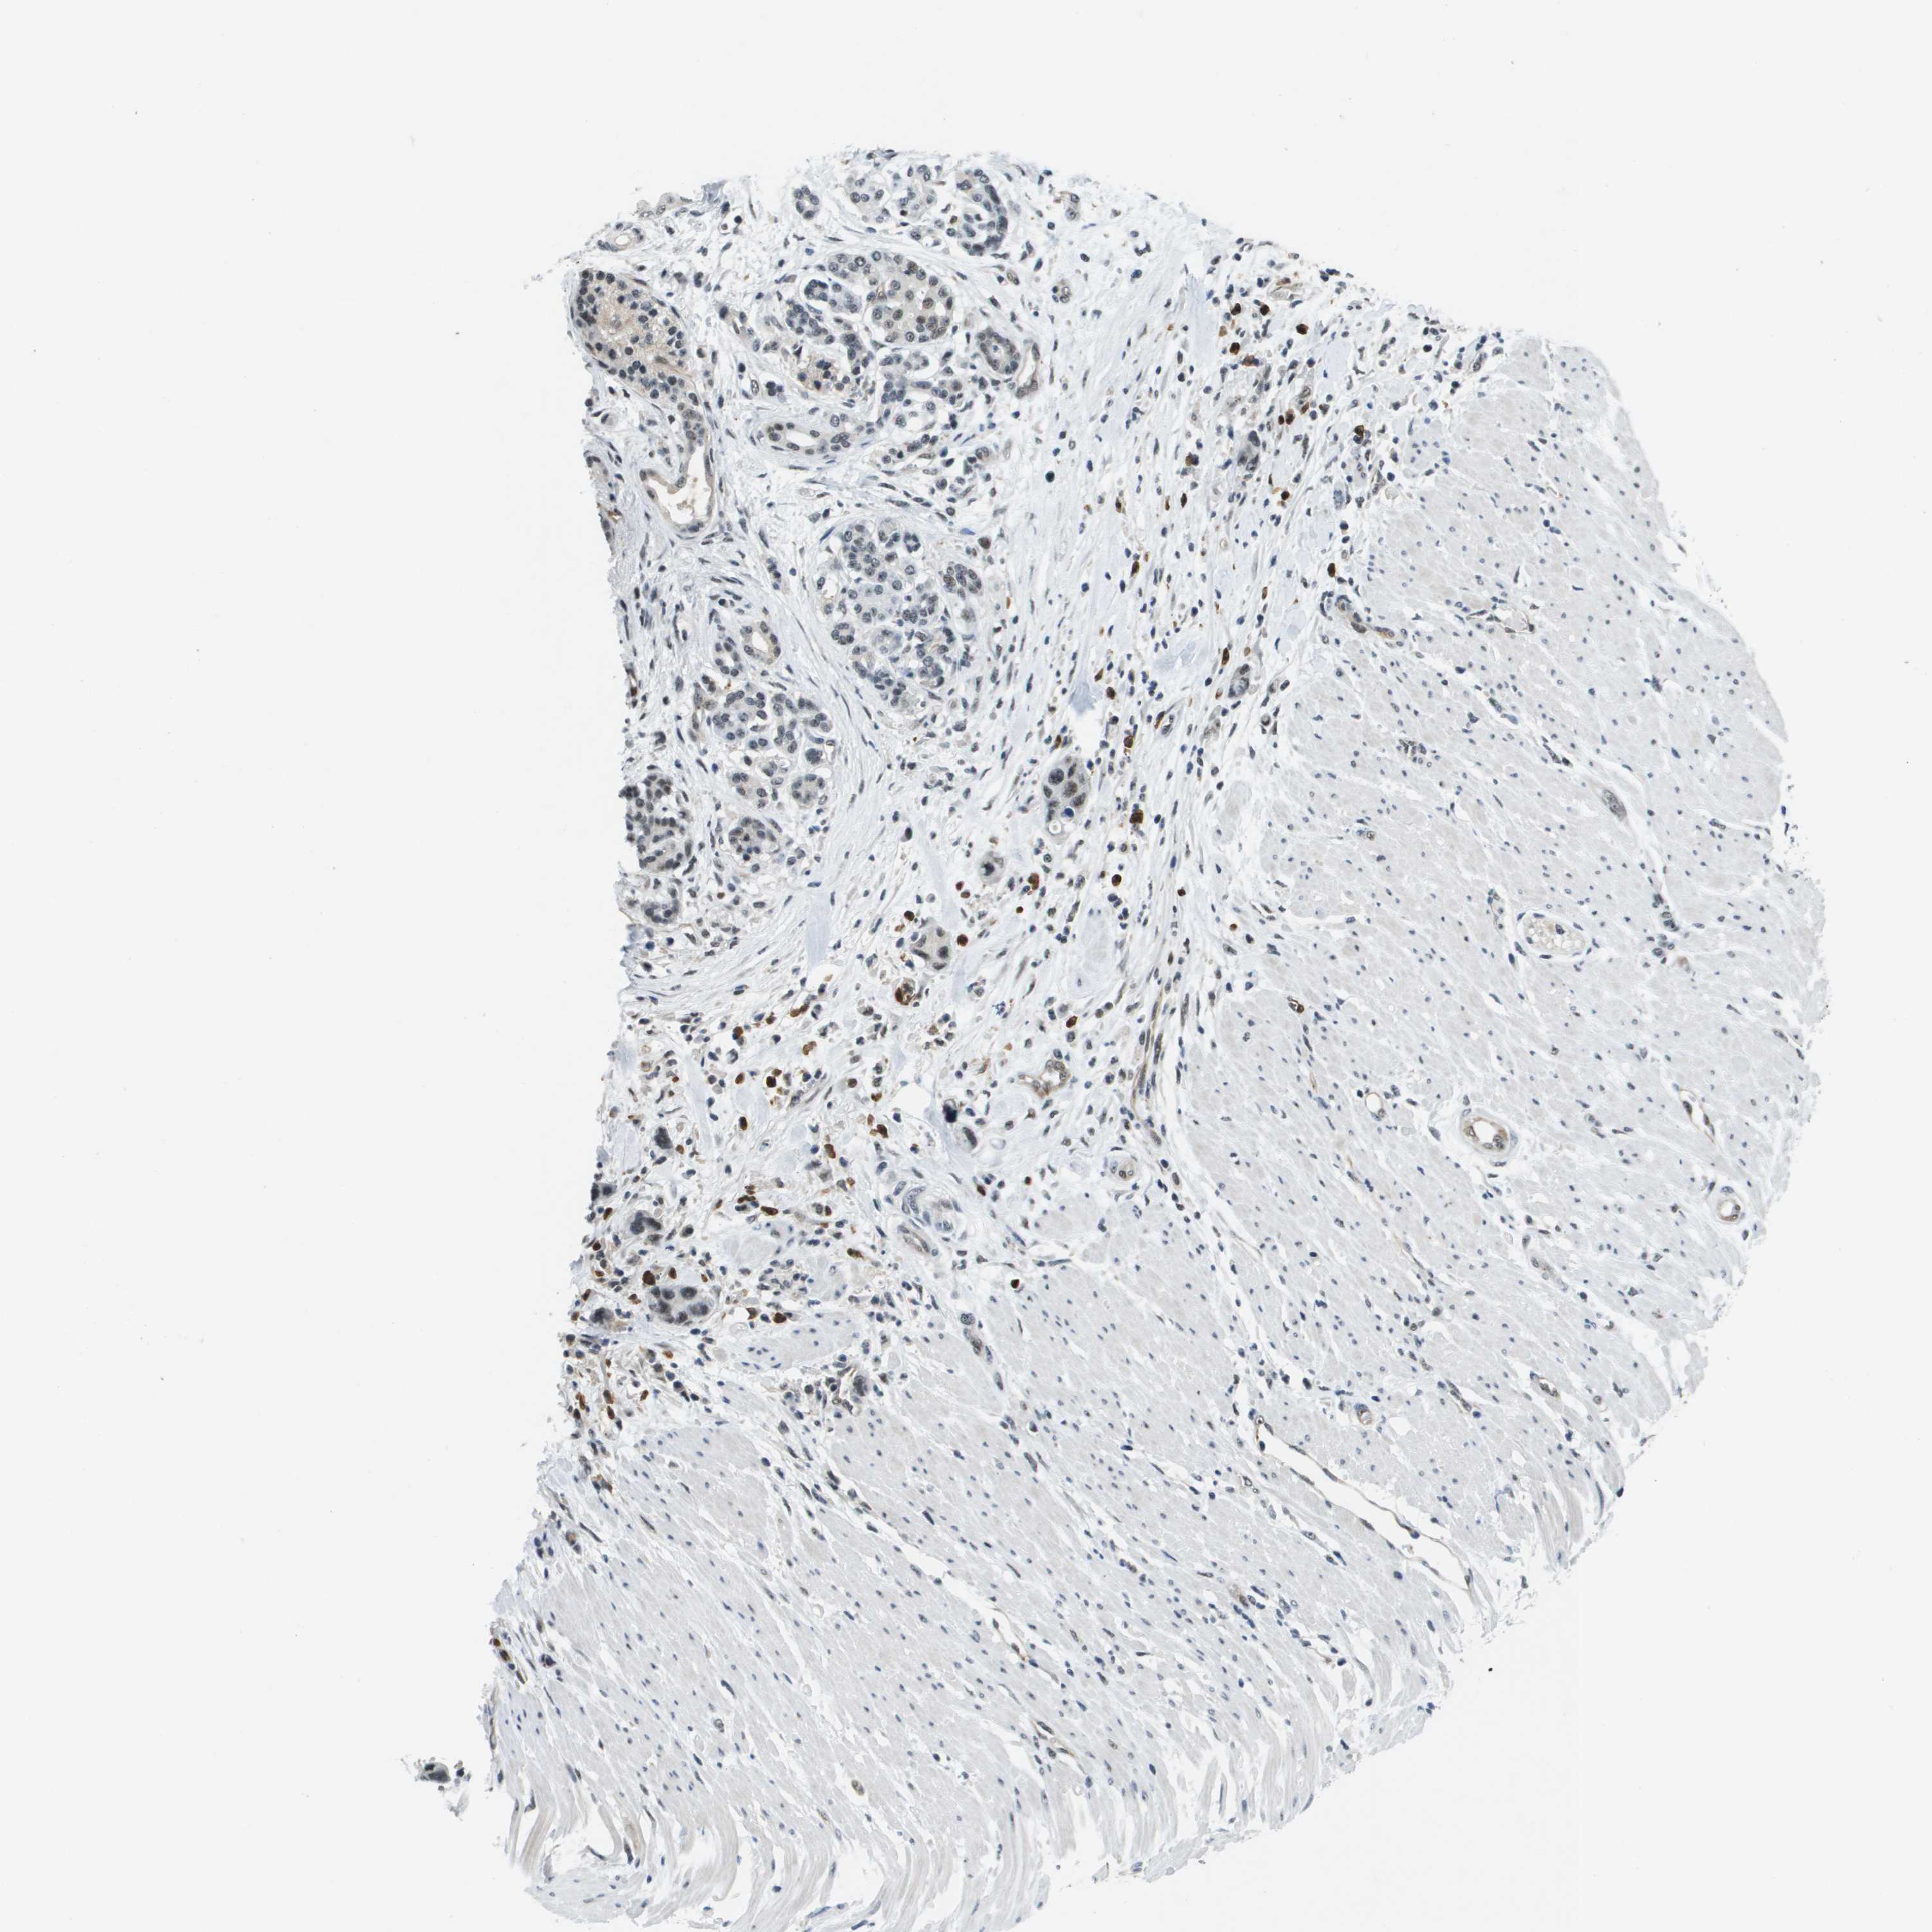

PANCREATIC CANCER - Protein expressioni

A mouse-over function shows sample information and annotation data. Click on an image to view it in a full screen mode. Samples can be filtered based on level of antibody staining by selecting one or several of the following categories: high, medium, low and not detected. The assay and annotation is described here.

Note that samples used for immunohistochemistry by the Human Protein Atlas do not correspond to samples in the TCGA dataset.

Antibody stainingi

Antibody staining in the annotated cell types in the current human tissue is reported as not detected, low, medium, or high, based on conventional immunohistochemistry profiling in selected tissues. This score is based on the combination of the staining intensity and fraction of stained cells.

Each image is clickable and will lead to virtual microscopy that enables deeper exploration of all samples and also displays staining intensity scores, fraction scores and subcellular localization as well as patient and tissue information for each sample.

Antibody HPA016704

Staining

High

Medium

Low

Not detected

Intensity

Strong

Moderate

Weak

Negative

Quantity

>75%

75%-25%

<25%

None

Location

Nuclear

Cytoplasmic/membranous

Cytoplasmic/membranous,nuclear

Adenocarcinoma, NOS